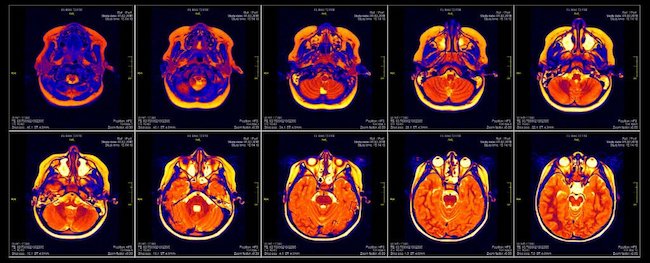

Este artículo públicado en el número de mayo de 2017 de la revista Journal of glaucoma evalúa la representación funcional retinotópica en la corteza visual en el glaucoma de ángulo abierto primario de leve a moderado y lo compara con controles sanos utilizando resonancia magnética funcional retinotópica de alta resolución dependiente del nivel de oxigenación (RMNf)

Se realizó RMNf en 9 participantes con glaucoma primario de Angulo abierto y se estudiaron 9 controles. Se utilizó una presentación visual de amplio espectro (± 55 grados) para evaluar la visión central y periférica. Se realizó un análisis de correlación entre los cambios de RMNf y las puntuaciones de campo visual, y entre los cambios de RMNf y los espesores de la capa de fibras nerviosas de la retina. Se realizó una comparación de los cambios de RMNf para los cuadrantes individuales del campo visual entre los subgrupos de Glaucoma primario de ángulo abierto y el grupo normal.

Los valores en la RMNf en los participantes con glaucoma primario de ángulo abierto en las regiones periféricas visuales se redujeron en comparación con los normales, pero fueron similares en las regiones visuales centrales, en consonancia con la noción de que la visión periférica se ve afectada antes y más en comparación con la visión central. La cartografía retinotópica de la RMNf reveló una mayor representación de la parafovea en la corteza visual de los participantes con glaucoma primario de ángulo abierto en comparación con los normales. La ampliación cortical de la representación visual central, pero no periférica, en la corteza visual fue mayor en los participantes con glaucoma primario de ángulo abierto, lo que sugiere una reasignación funcional. Los cambios En la RMNf de los cuadrantes individuales del campo visual se correlacionaron significativamente con las puntuaciones del campo visual y con el grosor de la capa de la fibra nerviosa de la retina en los cuadrantes correspondientes.

Glaucoma y actividades sociales